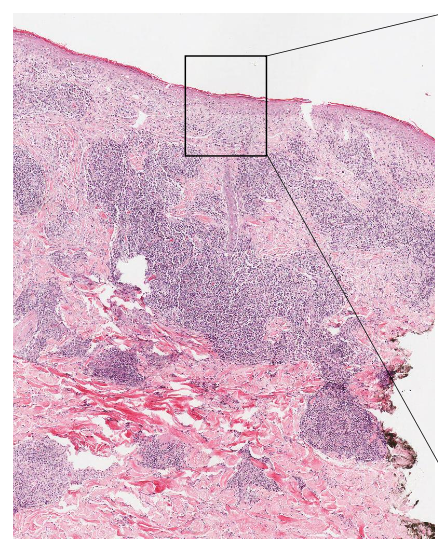

name the biological process shown in this image

chronic inflammation

lymphocytes